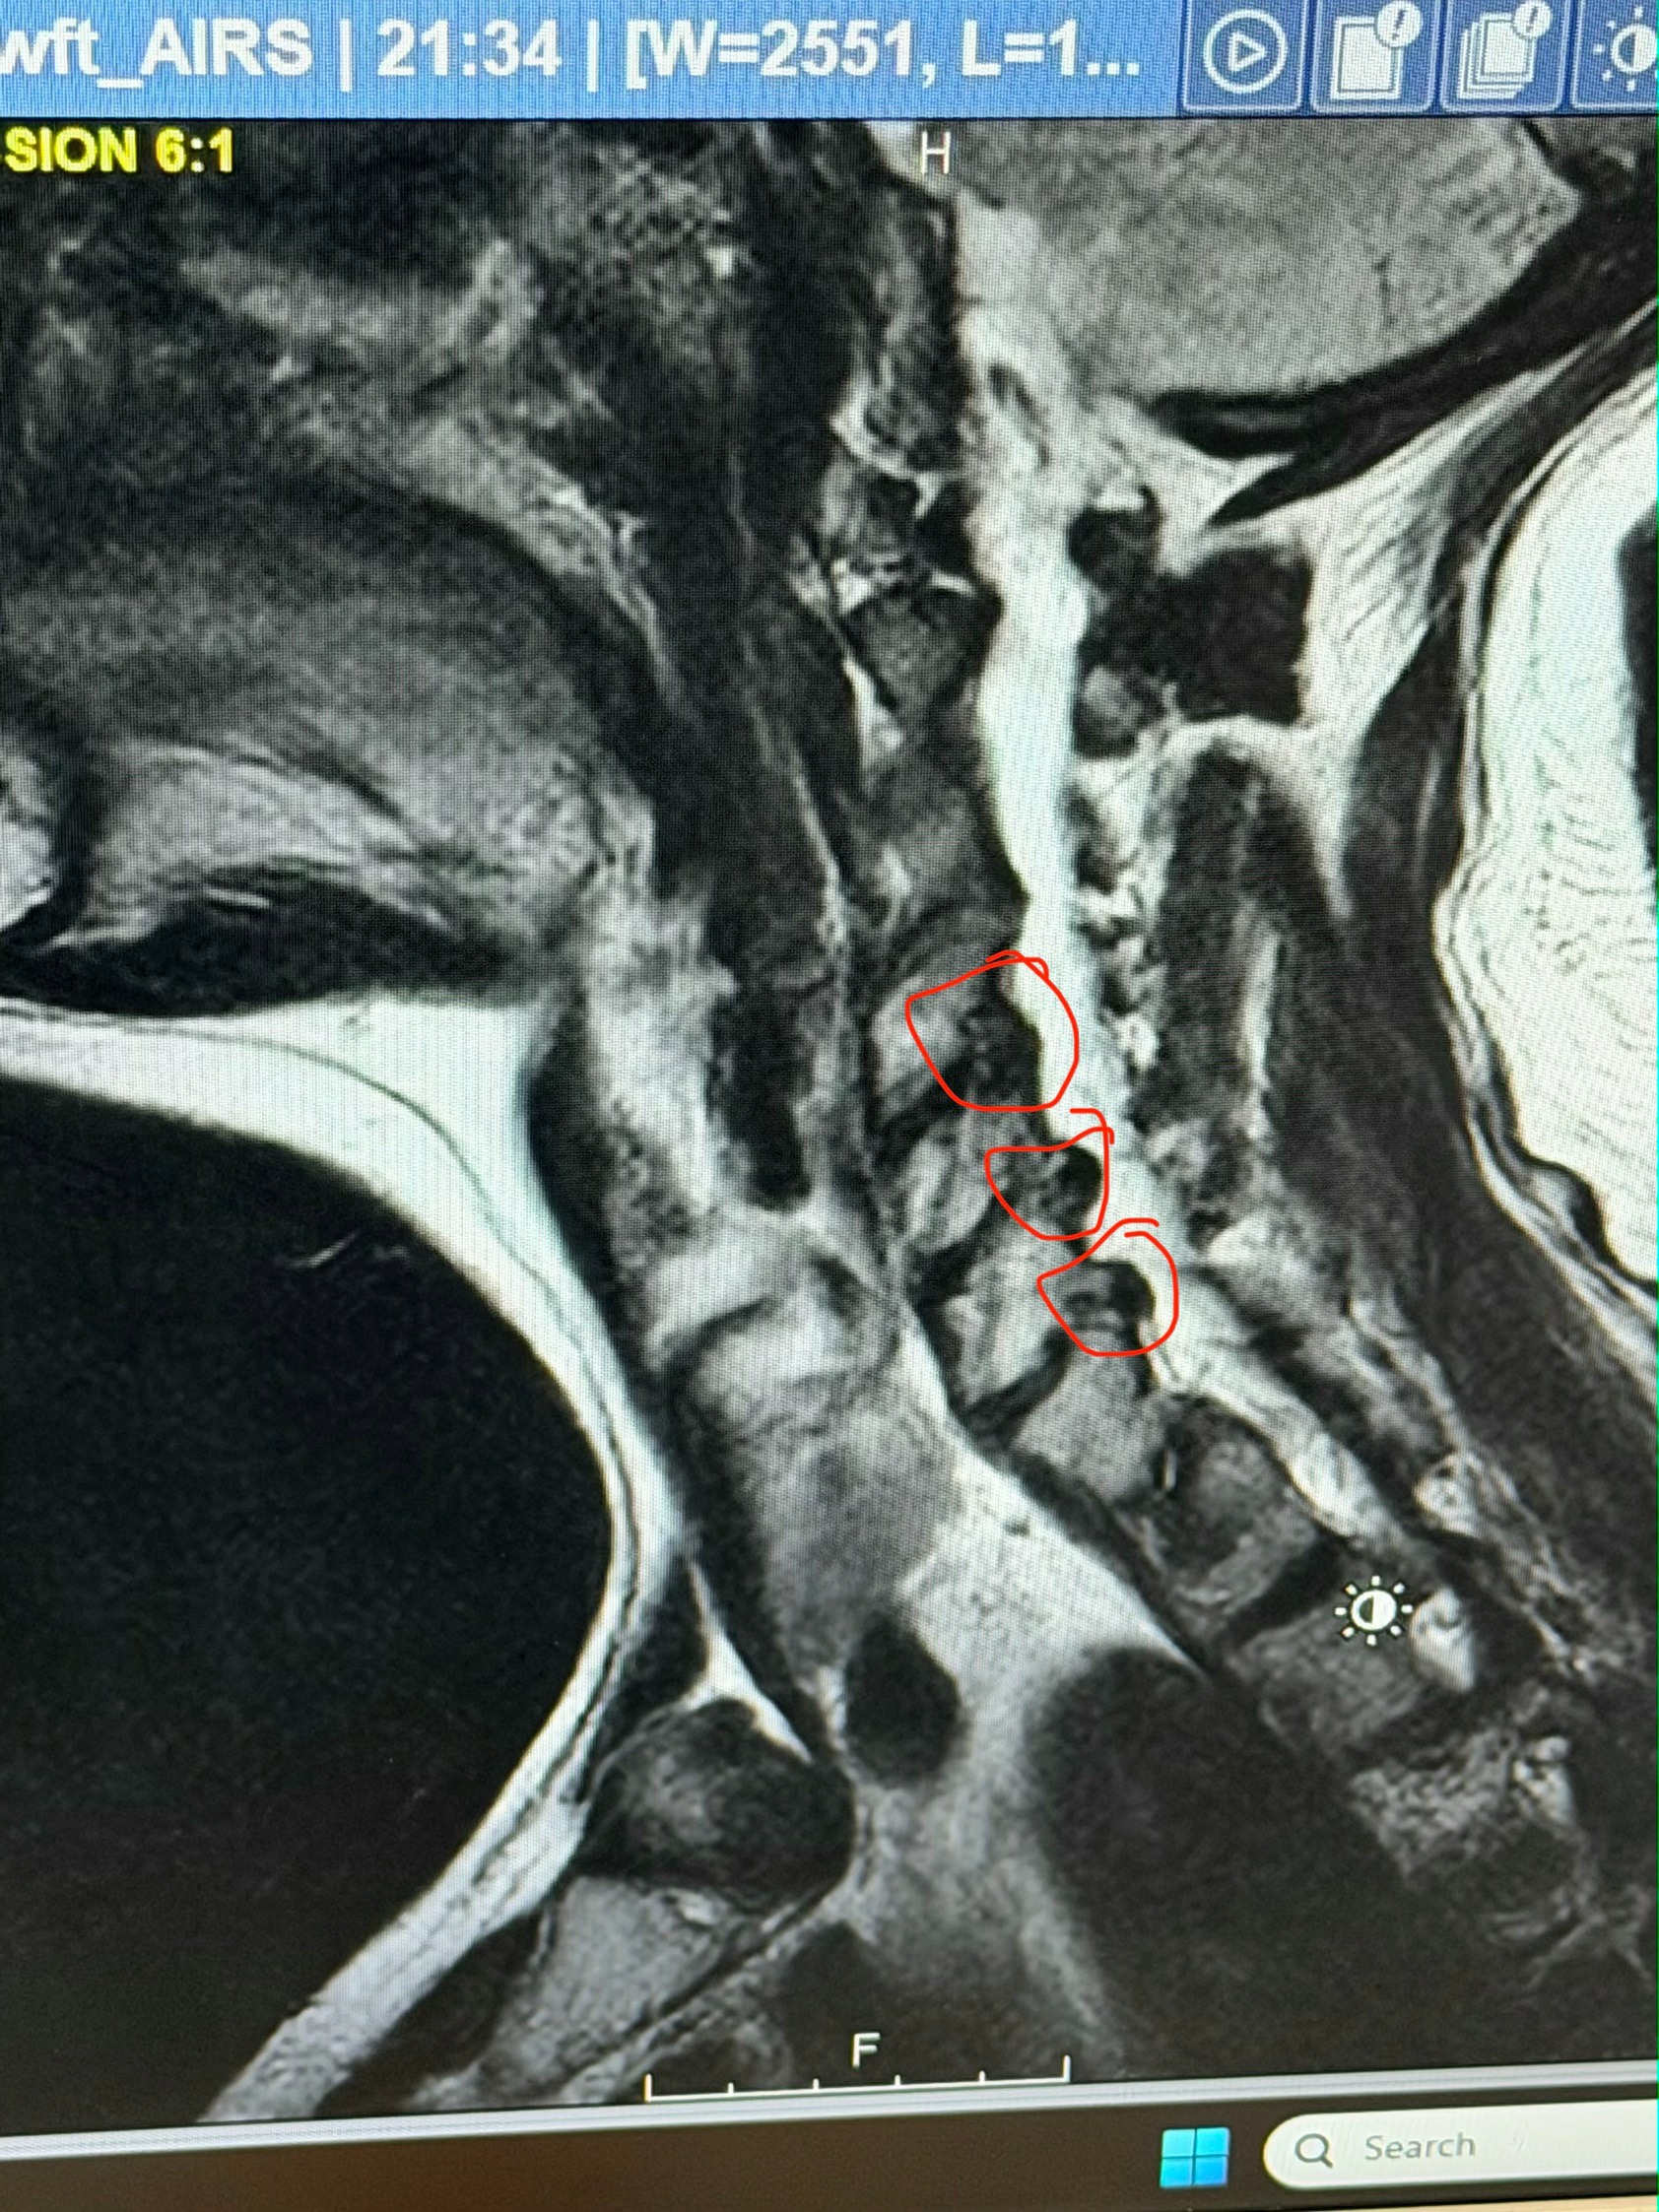

Gabe has always dealt with neck and back issues since childhood, and after years of carrying extra weight (at one point he reached 598 lbs), his spine has seen some wear and tear. Lately, he lost a lot of strength in his left arm—sometimes it tingles, hurts sharply, or goes numb. His MRI showed severe stenosis throughout his spine and several bone spurs pressing on nerves.

After months of MRIs, injections, specialists, and doing everything humanly possible to avoid surgery, the conclusion is very clear: Gabe needs cervical spinal fusion surgery at C5–C7. The discs between those vertebrae have degenerated to the point that there is significant compression on the nerves coming out of his spine. On top of that, there are three large bone spurs in that same area, which are further crowding the space and adding to the nerve compression. This combination has caused Gabe constant pain, electric-shock sensations, and numbness and tingling down his left arm—and more concerning, it has already begun to cause weakness and muscle atrophy. In other words, the nerves are being squeezed enough that the muscles they control aren’t getting proper signals, which means continuing to “push through” could lead to permanent loss of strength or function. At this point, surgery isn’t about comfort—it’s about preventing long-term damage. This isn’t optional; it’s necessary.